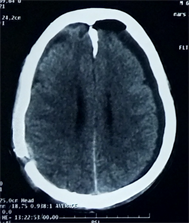

A 65-year-old man presented to the hospital with a 2-month history of recurrent headache requiring oral medication without noticeable improvement, and dizziness. There was an history of head injury from a traffic accident 3 months ago. His vitals parameters were within normal limits with no neurological deficits. The result of the Brain CT scan showed right frontal-parietal CSDH with mass effect associated to left frontal-parietal hygroma (Figure 1). After hospitalization and normal preoperative assessment, CSDH was evacuated through 2 burr holes and hygroma through 1 burr hole. Postoperatively the patient presented with agitation and headaches. CT scan is performed and showed an acute hematoma mimicking an extradural hematoma and frontal pneumocephalus (Figure 2). A

Figure 1. Brain CT scan found: Right frontal-parietal CSDH associated to left frontal-parietal hygroma.